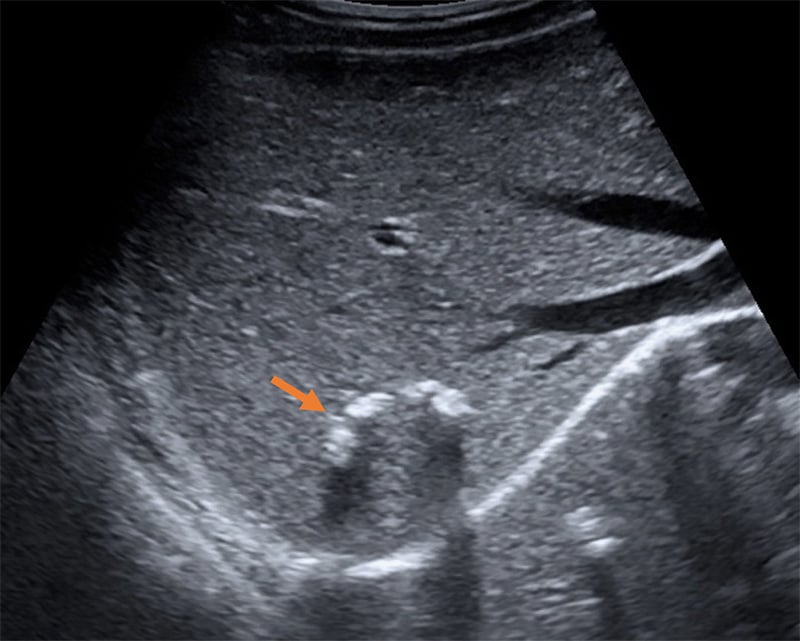

Figure 51. Severe hydronephrosis seen on long axis view of the kidney. Note the severe dilation of the renal pelvis and thinning of the renal cortex, as well as the dilated ureter extending to the right of the image.

Figure 52. Moderate hydronephrosis with ureteral dilation (extending deep from the renal pelvis).